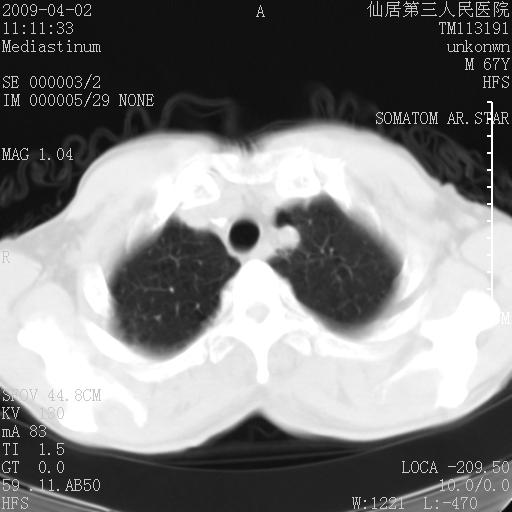

患者老年男性,乏力畏寒来诊,摄胸片示右下肺感染性病变,抗炎两周后复查胸片,无好转有进展。

后做ct平扫表现如下:

病灶呈蜂窝征,纵隔多个淋巴结肿大;肺泡癌需考虑

我认为普通的感染应该可以除外,间质性肺炎可能性较大,但如何解释纵膈的淋巴结肿大呢